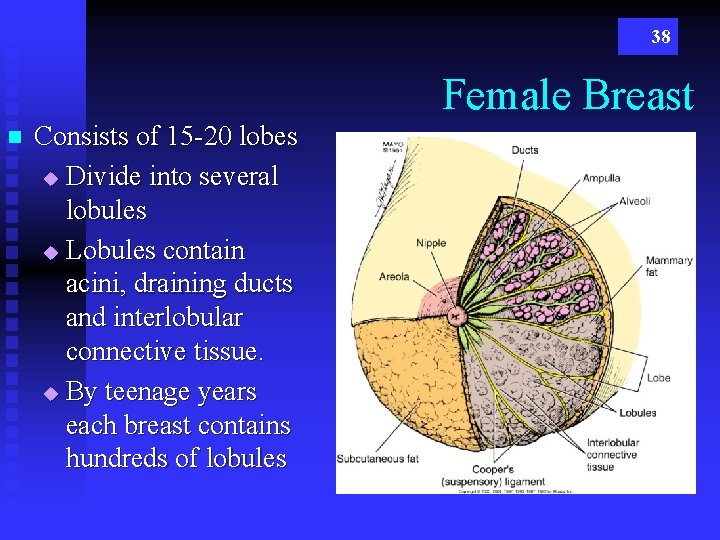

38 Female Breast n Consists of 15 -20 lobes u Divide into several lobules u Lobules contain acini, draining ducts and interlobular connective tissue. u By teenage years each breast contains hundreds of lobules

39 See Mammo Study Guide TDLU ? COOPER’S Ligaments